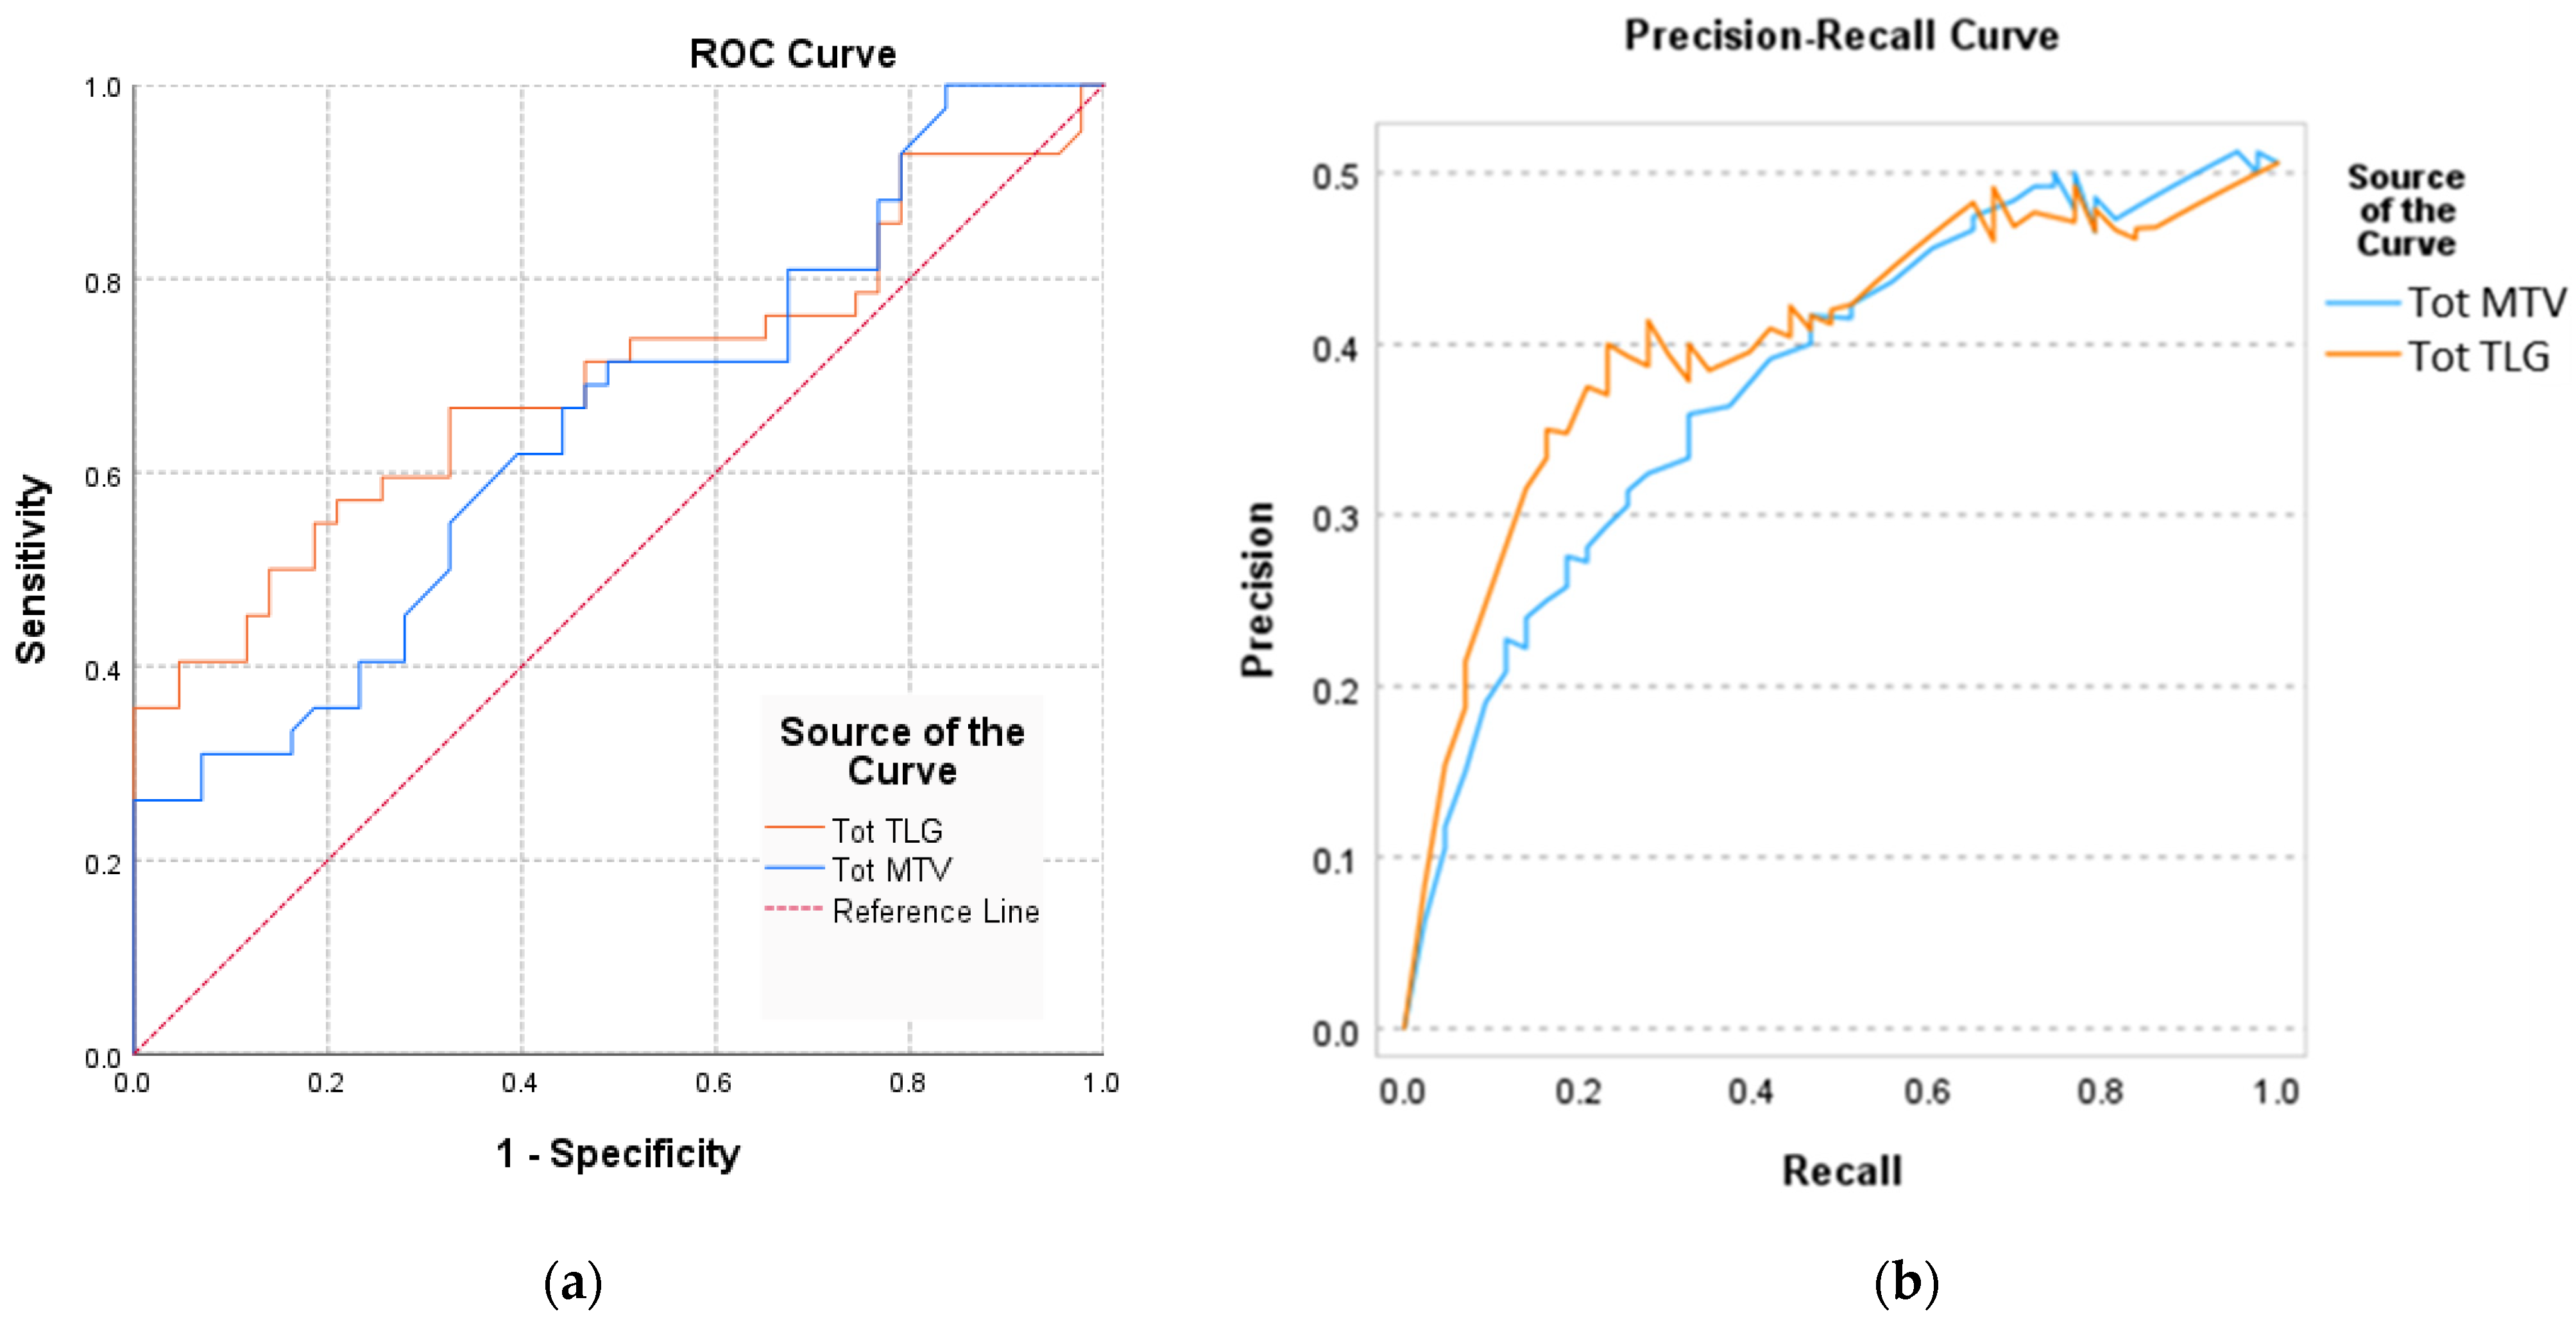

| Area under the Curve AUC (95%CI) | Std. Error | p-Value | |

|---|---|---|---|

| Tot MTV | 0.694 (0.579–0.809) | 0.059 | 0.001 * |

| Tot TLG | 0.721 (0.654–0.832) | 0.062 | 0.013 * |

| Sensitivity | 95% CI | Specificity | 95% CI | PPV | NPV | Cutoff | |

|---|---|---|---|---|---|---|---|

| Tot MTV | 0.79 | 0.67 to 0.91 | 0.75 | 0.69 to 0.87 | 0.85 | 0.83 | 49.8 |

| Tot TLG | 0.89 | 0.71 to 0.92 | 0.76 | 0.68 to 0.94 | 0.73 | 0.87 | 72.1 |